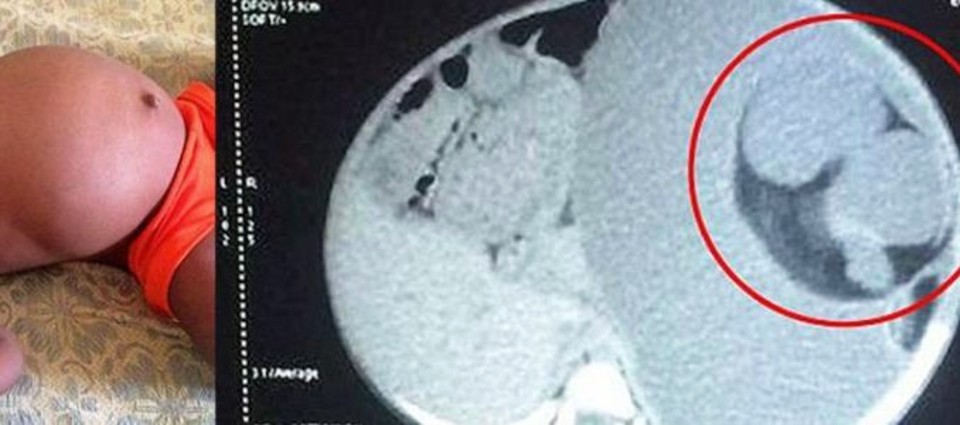

A 15-month-old girl was taken to hospital after her stomach swelled a lot, although she could not keep food or liquids in it. Her parents were poor but hardworking, they ignored this problem as much as they could, hoping that one day it would go away on its own. When they realized it wasn’t going to go away, they knew they needed help.

The doctors believed, at first sight, that the little girl definitely has a tumor in her abdomen, so they put her, after a few tests, directly in the operation. But the surgeon couldn’t believe what he found as soon as they cut the little girl. It wasn’t a tumor, it was her own twin brother.

This type of meal is called “parasitic brother” and had been attached to the girl’s stomach since her mother’s womb, feeding on the girl! The disease is also called “Fetus in fetus” and is very rare, there were only 200 such cases worldwide.

The mass that exists in these children usually has bones, muscles, and hair. The surgeons removed it from the girl’s stomach and then weighed her, she weighed over 3 kilograms, the weight of a baby at birth!

It seems that the operation was complicated by the fact that some organs of the face were joined with the organs of the parasitic twin, here is what the surgeon said: there were blood vessels all over the structure. So we had to remove blood vessels and move the organs, to separate them from the fetus, without damaging them ”.

Before the operation, the baby weighed 8 kilograms, after the operation, she lost almost half of her weight.